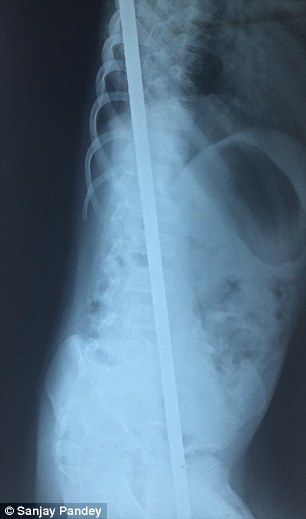

Aman si trovava sul tetto della sua casa ad Kaushambi nell’Uttar Pradesh (India) per fare dei lavoretti. Quando la struttura crollò, il piccolo cadde da tre metri e mezzo di altezza finendo sull’asta. Il metallo, lungo un metro e venti, entrò dalla coscia e attraversando il torace uscì dalla schiena. Gravissimi furono i danni riportati dal suo organismo. Venne lacerato un grande vaso sanguigno, furono trafitti intestino e diaframma, e un polmone rimase danneggiato. La colonna vertebrale si è “salvata” per pochi millimetri. Portato d’urgenza al Narayan Swaroop Hospital dalla madre 30enne, Kamla Devi, il piccolo ha affrontato un complicatissimo intervento chirurgico durato 4 ore.

La possibilità di sopravvivere ad un simile incidente è una su un miliardo. Aman però ha battuto le statistiche, anche se il percorso per lui è ancora molto lungo. Per il momento il piccolo non può riprendere la vita che svolgeva prima di quel tragico giorno d’ottobre. Secondo i medici, ci vorrà ancora molto tempo prima che possa andare in bagno. Inoltre, potrebbe soffrire di disfunzione erettile. I danni polmonari saranno quasi certamente fonte di problema per le attività sportive. Sono anche probabili formicolii a mani e piedi, e mancanza di coordinamento motorio. Una lunga lista di danni conseguenti all’incidente, ma nulla se si pensa al fatto che Aman vive per una questione di millimetri.